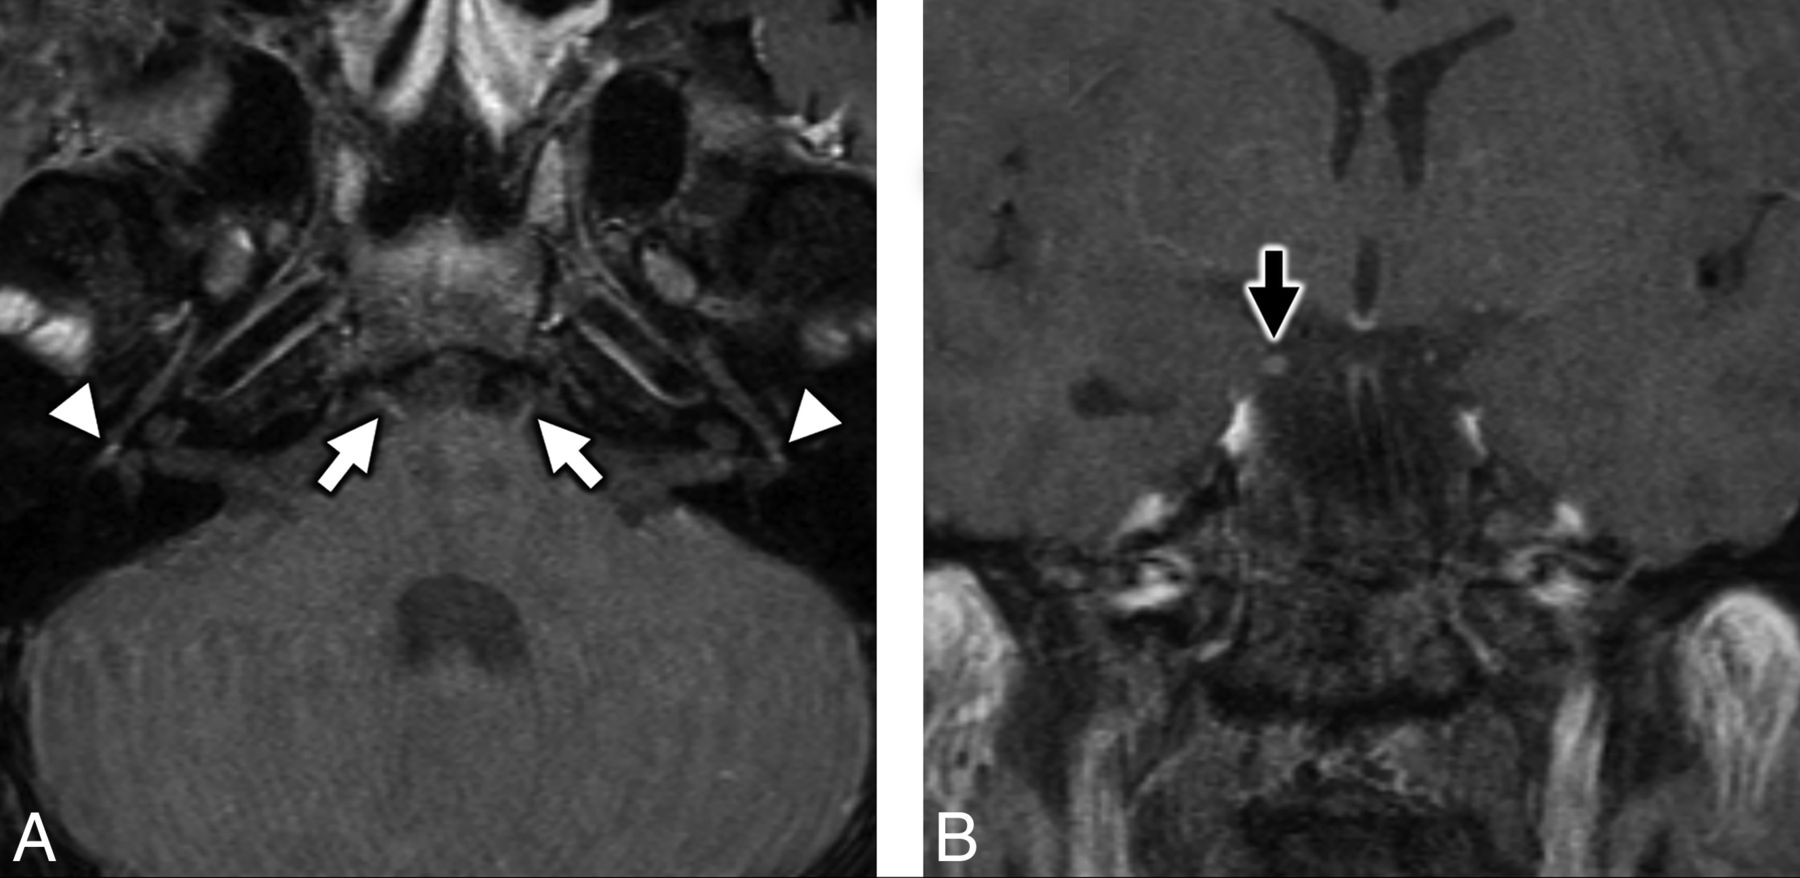

A 21-year-old man presented to the emergency department with progressive 4-day history of fever, cough, dyspnea, diarrhea, nausea, headache, and sinonasal congestion. Aside from a medical history of hypertension, prediabetes, and class I obesity, the patient was otherwise healthy and denied tobacco, alcohol, substance abuse, or recent travel. Vital signs were remarkable for a body temperature of 37.5°C, blood pressure of 116/57 mm Hg, pulse of 76 beats per minute, and oxygen saturation of 95% on room air. Physical examination documented nonlabored respirations and clear lungs. Neurologic examination was intact. Chest radiographs (Fig 1) demonstrated patchy bilateral air space opacities without lobar consolidation.

Initial chest radiographs in a patient with COVID-19 and subsequent bifacial weakness and paresthesia subtype Guillain-Barré syndrome. Posterior-anterior (A) and lateral (B) upright chest radiographs demonstrate low lung volumes with patchy bilateral air space opacities, but no lobar consolidation.

During the next 24 hours, the patient experienced increased dizziness with oxygen saturation falling into the mid-80s documented by pulse oximetry. He returned to the emergency department febrile (body temperature of 39.1°C), mildly tachycardic (102 beats per minute), tachypneic (28 breaths per minute), and hypoxic (89% on room air). Chest radiographs demonstrated increased bilateral air space opacities, and a complete blood count revealed lymphopenia (absolute lymphocyte count of 0.7 K/mm3). He was admitted for oxygen support and monitoring, and blood oxygenation was weaned from 2 L by nasal canula to room air. He was discharged home on hospital day 4, and his sent-out testing confirmed COVID-19 positivity the day after discharge.

At the initial emergency department visit, chest radiography (Fig 1) was performed, and nasopharyngeal swab specimens were sent for multiplex reverse transcription polymerase chain reaction via a NxTAG Respiratory Pathogen Panel (Luminex) to assess adenovirus, influenza A, influenza B, parainfluenza 1, parainfluenza 2, parainfluenza 3, parainfluenza 4, Chlamydia pneumoniae, Mycoplasma pneumoniae, bocavirus, coronavirus, respiratory syncytial virus A, respiratory syncytial virus B, metapneumovirus, rhinovirus, and enterovirus infection (On-line Table 5). Additional nasopharyngeal and oropharyngeal swab specimens were sent to an outside private laboratory (Viracor Eurofins Clinical Diagnostics) for SARS-CoV-2 real-time reverse-transcriptase polymerase chain reaction testing. During subsequent hospital readmissions and before final discharge, COVID-19 status was tested with nasopharyngeal/oropharyngeal swabs and SARS-CoV-2 PCR assays performed at our hospital laboratory.